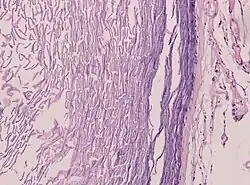

Haut

Epidermoidzysten sind in der Lederhaut lokalisierte gutartige Zysten, die aus Zellen der Oberhaut (Epidermis) bestehen, jedoch keine Hautanhangsgebilde aufweisen. Diese Zysten entstehen durch die Zellproliferation von Epidermalzellen in der sie umgebenden Lederhaut. Histologisch bestehen sie aus einer dünnen Plattenepithelschicht mit Hornlamellen, die zum Teil abgeschilfert sein können. Bei Hautverletzungen können kleinere Teile der Oberhaut in die Tiefe der Wunde verlagert werden. Diese verpflanzten Epidermisteile wachsen im Inneren der Wunde weiter und bilden Hornsubstanz, welche dann zur Entstehung einer Epidermoidzyste führt.